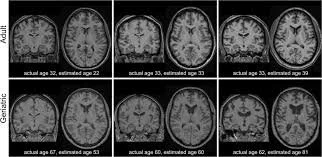

Brain age is a computational estimate of how old a brain appears based on structural MRI features, compared to large reference datasets. When brain age exceeds chronological age, it has been associated with:

• Higher risk of cognitive decline

• Increased Alzheimer’s disease risk

• Poorer overall brain health trajectories

Brain age is not a diagnosis. It is a biomarker—a signal that reflects how the brain has adapted to decades of lifestyle, metabolic, and health exposures.

• A higher visceral fat–to–muscle ratio was associated with older brain age

• Higher muscle mass was associated with younger brain age

• Subcutaneous fat showed no significant relationship with brain age

More muscle + less hidden belly fat = younger-looking brains